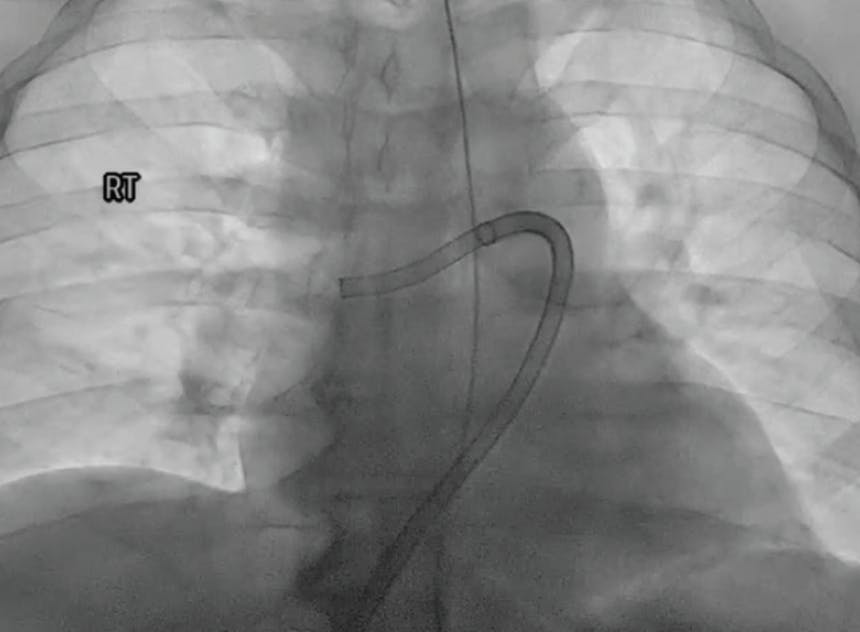

INTERVENTION

Based on evaluation, we decided to pursue aspiration thrombectomy utilizing Lightning Flash through a 16-F, 65-cm Gore DrySeal sheath (Gore & Associates). We achieved access in the right femoral vein. The device time was 17 minutes, and the total procedure time was 30 minutes (Figure 3, Figure 4, Figure 5, and Figure 6). At the conclusion of the case, the total EBL was 175 mL, the patient had BP of 112/67 mm Hg, HR of 65 bpm, and oxygen saturation of 99% on 3 L nasal cannula.

Based on the evaluation, the decision was made to pursue aspiration thrombectomy using the Lightning Flash device. The opening PA pressures were 33/12 mm Hg (mean, 20 mm Hg) and closed with 18/3 mm Hg (mean, 8 mm Hg), taken through the 16-F, 65-cm Gore DrySeal sheath, showing a significant drop in pressure. The device time of Lightning Flash was 6 minutes, and the total procedure time was 55 minutes (Figure 3, Figure 4, and Figure 5). By the conclusion of the case, the EBL was 100 mL and postprocedure BP was 122/63 mm Hg, HR was 54 bpm, and oxygen saturation was 97% on 2 L nasal cannula.

After initial evaluation, the decision was made to use aspiration thrombectomy to remove the PE thrombus. We utilized a 16-F, 65-cm Gore DrySeal sheath through the right femoral vein. Penumbra’s Lightning Flash was used for a device time of 10 minutes (Figure 3, Figure 4, and Figure 5). The total procedure time was only 20 minutes. With the conclusion of the case, we had an EBL of 120 mL and a postprocedure BP of 120/87 mm Hg. The HR decreased substantially to 98 bpm, and the oxygen saturation improved to 100% on room air.